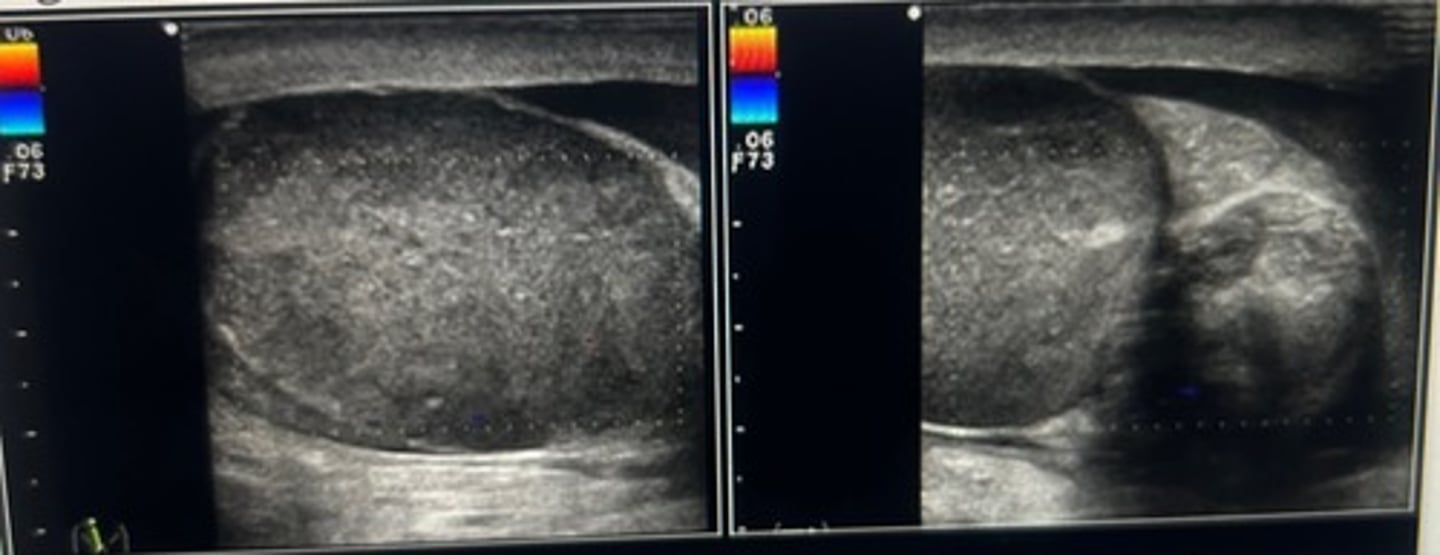

When using color Doppler to compare, testicular perfusion, you should always

use the dual screen function to demonstrate an image of both testicles